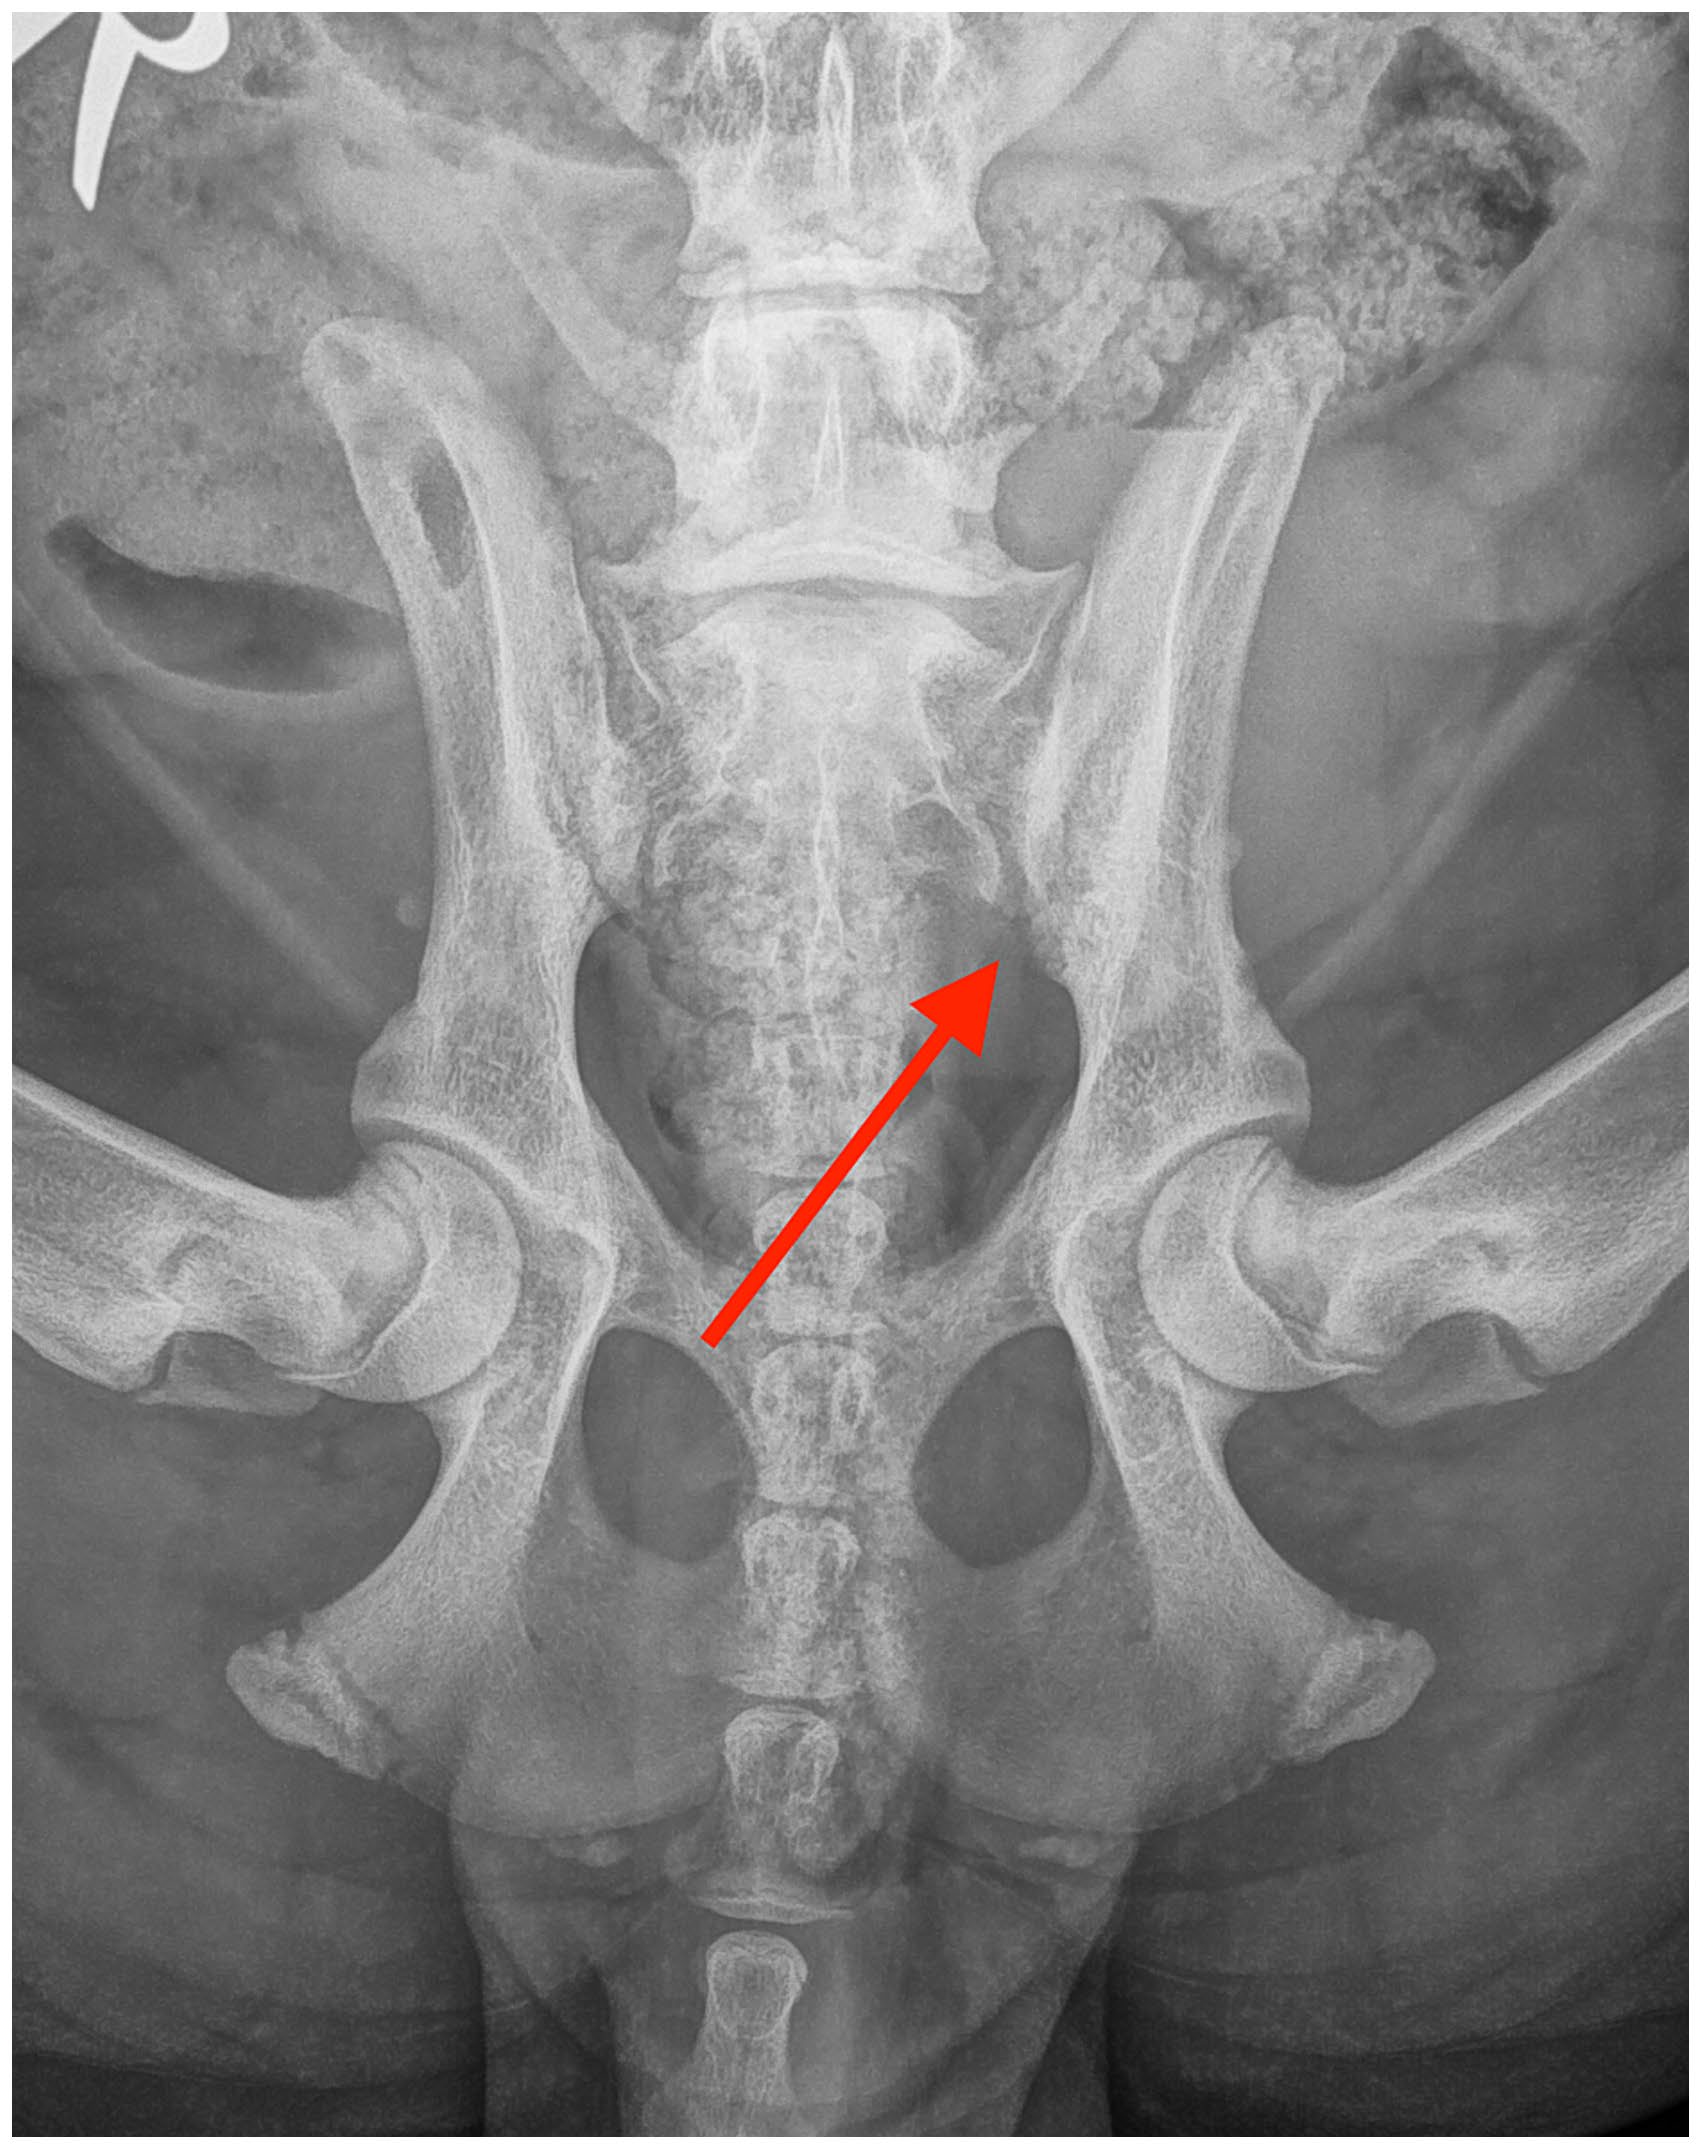

6周后,X光片显示侵蚀性病变的范围显著缩小,骨骼密度整体增加,骶髂关节间隙变窄(下图)。X光片上病变的缓解尚不完全。继续进行物理治疗,并允许恢复正常的活动。

↑ 腹背位X光片显示骶髂关节的侵蚀性病变有轻度改善(红色箭头)。